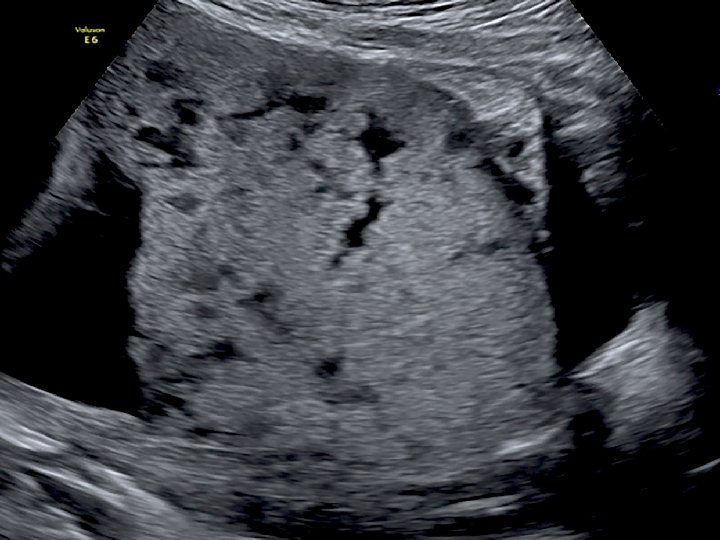

FETAL BÜYÜME BOZUKLUKLARINDA TARAMA VE TANI • Fetal büyüme bozukluklarının taranmasında medikal ve obstetrik öyküyü takiben fizik muayenede gebeliğin 24 - 38. haftaları arası uterus fundus yüksekliğinin ölçümü kullanılmaktadır. • Anormal fetal büyüme tipik olarak ultrasonografide fetusun güncel biyometrik ölçümleri ile gestasyonel yaş için beklenen biyometrik ölçümleri arasında tutarsızlık olması ile tanınır. • Tanı büyük ölçüde doğru gebelik haftasını belirlemeye bağlıdır!

• Anormal biyometri saptanan hastalarda anormal fetal büyümenin fetal, plasental veya maternal nedenlerinin belirlenmesi amacıyla klinik ve ultrasonografik muayene yapılması gerekir. • Tahmini fetal ağırlığın saptanması için birçok formül önerilmiştir. • Bu formüllerin birçok parametre içermesine (biparietal çap, oksipitofrontal çap, baş çevresi, femur uzunluğu, abdominal çap ve abdominal çevre) karşın tahmini fetal ağırlıkta yanılma ortalama %10 -15 arasındadır ve bu oran %25’e kadar çıkabilmektedir.

• Gebelik yaşının tespitinde erken gebelikte en değerli ultrasonografik ölçüm parametresi CRL’dir. • İkinci trimesterda ise BPD ve HC daha doğru sonuçlar verir. • Üçüncü trimesterda ise en değerli ölçüm AC’dir. AC fetal büyüme ve ağırlık için en değerli parametredir.